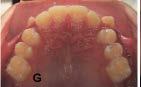

Tratamiento de caninos retenidos superiores en paciente en crecimiento con clase II división 2. Reporte de caso clínico

Los caninos retenidos constituyen una alteración eruptiva frecuente, con mayor prevalencia en la arcada superior. Su etiología es multifactorial y puede interferir con el trayecto normal de erupción, comprometiendo la oclusión y la estética.

Objetivo: Corregir una maloclusión Clase II división 2 mediante tratamiento ortodóntico en un paciente en crecimiento con ambos caninos superiores retenidos. Metodología: Se presenta el caso de un paciente masculino de 12 años, en dentición permanente, con perfil convexo, patrón dolicofacial y Clase II esquelética. Se realizó tratamiento ortodóntico sin extracciones. Para la tracción y alineación de los caninos retenidos se emplearon resortes abiertos (open coil springs) para la creación de espacio. Resultados: